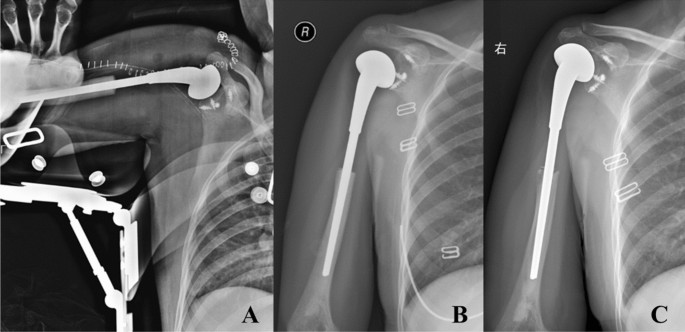

The patient was in supine position and the anterior incision of proximal upper arm was performed. The original biopsy pathway was resected. The resection range was determined according to the preoperative imaging examinations. The osteotomy plane of the humerus was design as 3–5 cm away from the edge of tumor and thus the extensive resection of the proximal humerus tumor was performed. After resection, the shoulder prosthesis (Chunli Zhengda Technology Co., Ltd) reconstruction was performed and the prosthesis was fixed by bone cement. The non-absorbable mesh patch and anchors were not used in the early cases. In the later stage, the traditional method of prosthesis reconstruction was innovated. The non-absorbable mesh patch and anchors were used in the reconstruction in 27 cases. The prosthesis was wrapped with mesh (Bard Crurasoft Patch) to repair the joint capsule, and the surrounding muscles such as pectoralis major, biceps brachii, brachii and triceps brachii were sutured on mesh patch (Fig. 2). On this basis, four anchors (DePuy Mitek FASTIN) were fixed in different directions (upper, lower, front and back) of the glenoid to improve the postoperative relative stability of the prosthetic humeral head and the shoulder glenoid (Fig. 3).

The postoperative radiography (A) showed 4 anchors were fixed in different directions (upper, lower, front and back) of the glenoid to restore the stability of the prosthesis. The radiography 3 months postoperative (B) and the radiography 104 months postoperative (C) showed the prosthesis was in stable position without obvious loosening and dislocation.